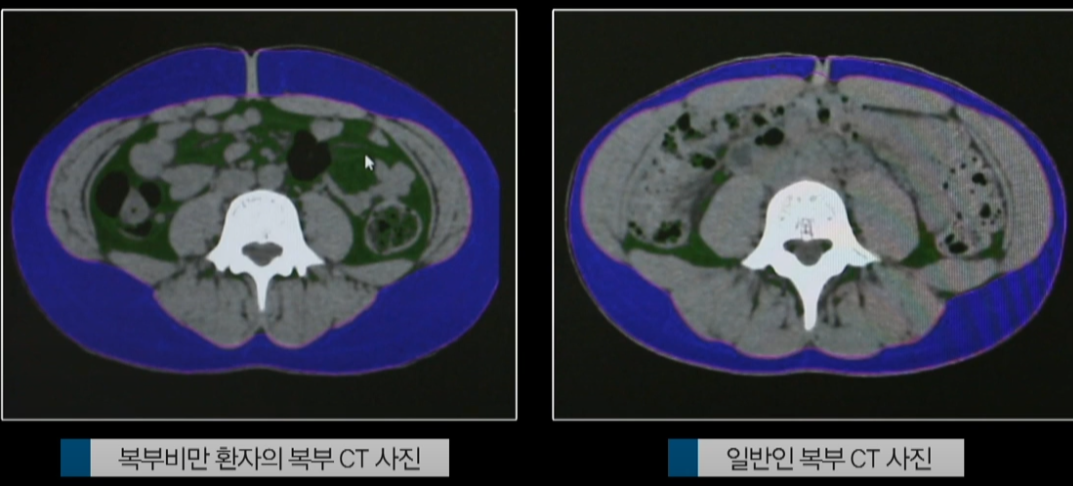

복부비만이란 말 그대로 복부에 지방이 과도하게 쌓인 상태를 말합니다.

겉보기에도 배가 볼록 나와 보이지만, 문제는 그 내부!

피하지방뿐만 아니라 장기 사이사이에 낀 내장지방이 건강에 훨씬 더 위험합니다.